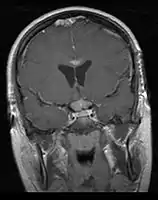

- Mainly located in midline structures, suprasellar region or pineal gland, also basal ganglia and hypothalamus

- Bifocal germinomas (synchronous suprasellar and pineal tumors) regarded as M+ in USA but M0 in Europe

- Toronto; 2006 (1995-2004) PMID 16530340 -- "Limited-field radiation for bifocal germinoma." (Lafay-Cousin L, Int J Radiat Oncol Biol Phys. 2006 Jun 1;65(2):486-92.)

- Retrospective. 6 patients with bifocal germinoma (pineal + suprasellar). All with diabetes insipidus at presentation. Treated with chemo followed by limited-field RT (whole ventricle 24-40 Gy +/- boost). Median F/U 4 years

- Conclusion: Bifocal germinoma can be considered locoregional rather than metastatic disease